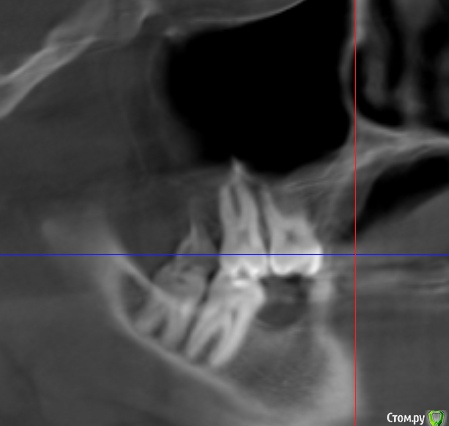

alex889 Опубликовано 8 февраля, 2020 Поделиться Опубликовано 8 февраля, 2020 Подскажите, над предпоследним зубом сверху это инородное тело в гайморовой пазухе? Это могло попасть при лечении каналов зуба мудрости? Может ли такое инородное тело вызывать боли и воспаление в челюстно-лицевой области?Файл КТ: http://fayloobmennik.cloud/7384939 Ссылка на комментарий

wladdX Опубликовано 10 февраля, 2020 Поделиться Опубликовано 10 февраля, 2020 (изменено) Инородных тел не нашёл. То что Вы приняли за инородное тело - перегородка в пазухе Изменено 10 февраля, 2020 пользователем wladdX 1 Ссылка на комментарий